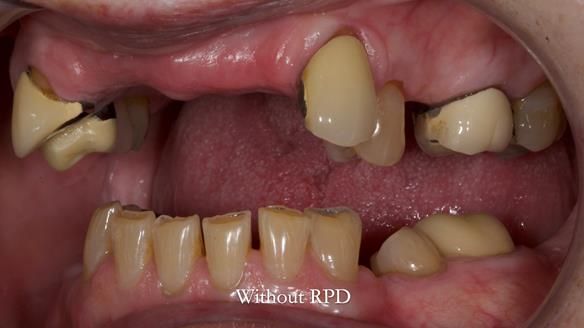

This is one of those cases that reminds me why I love removable prosthodontics. Pam was an absolute joy to treat — we were on the same page throughout. Her old upper flexible denture was loose, uncomfortable, and unaesthetic. We replaced it with a carefully designed metal-based upper partial denture/splint and new porcelain-bonded-to-zirconia (PBZ) crowns for the canines. The result is stable, comfortable, and natural-looking.

- Diagnosis and plan – Flexible upper denture ill-fitting with poor stability, retention, and appearance. Plan: metal-based upper partial denture/splint with lighter porcelain-bonded-to-zirconia crowns on UR3 and UL3.